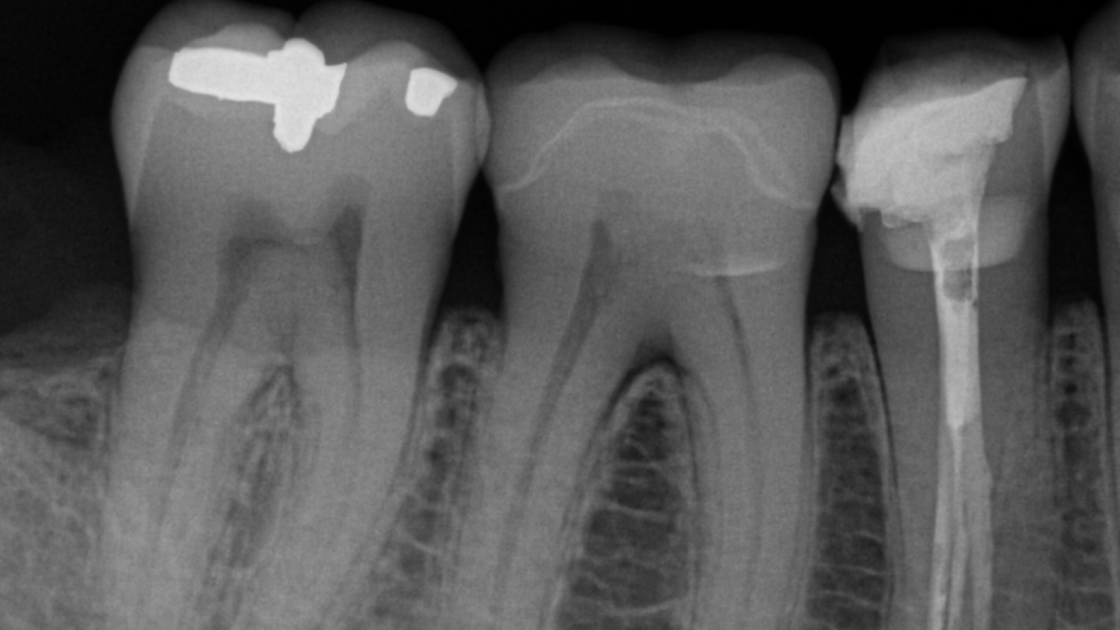

Если вам нужны интраоральные рентгеновские снимки для оценки симптоматической области или текущего эндодонтического лечения, в семействе интраоральных продуктов Dentsply Sirona найдется подходящее решение для вашего рабочего процесса. Ассортимент интраоральных рентгеновских аппаратов был разработан для того, чтобы помочь вам достичь точности при съемке рентгенограмм, особенно когда речь идет о позиционировании системы. Наши интраоральные рентгеновские аппараты также оптимизированы для легкой интеграции и оптимизации рабочих процессов, благодаря современному оцифровыванию и бесшовной автоматизации.